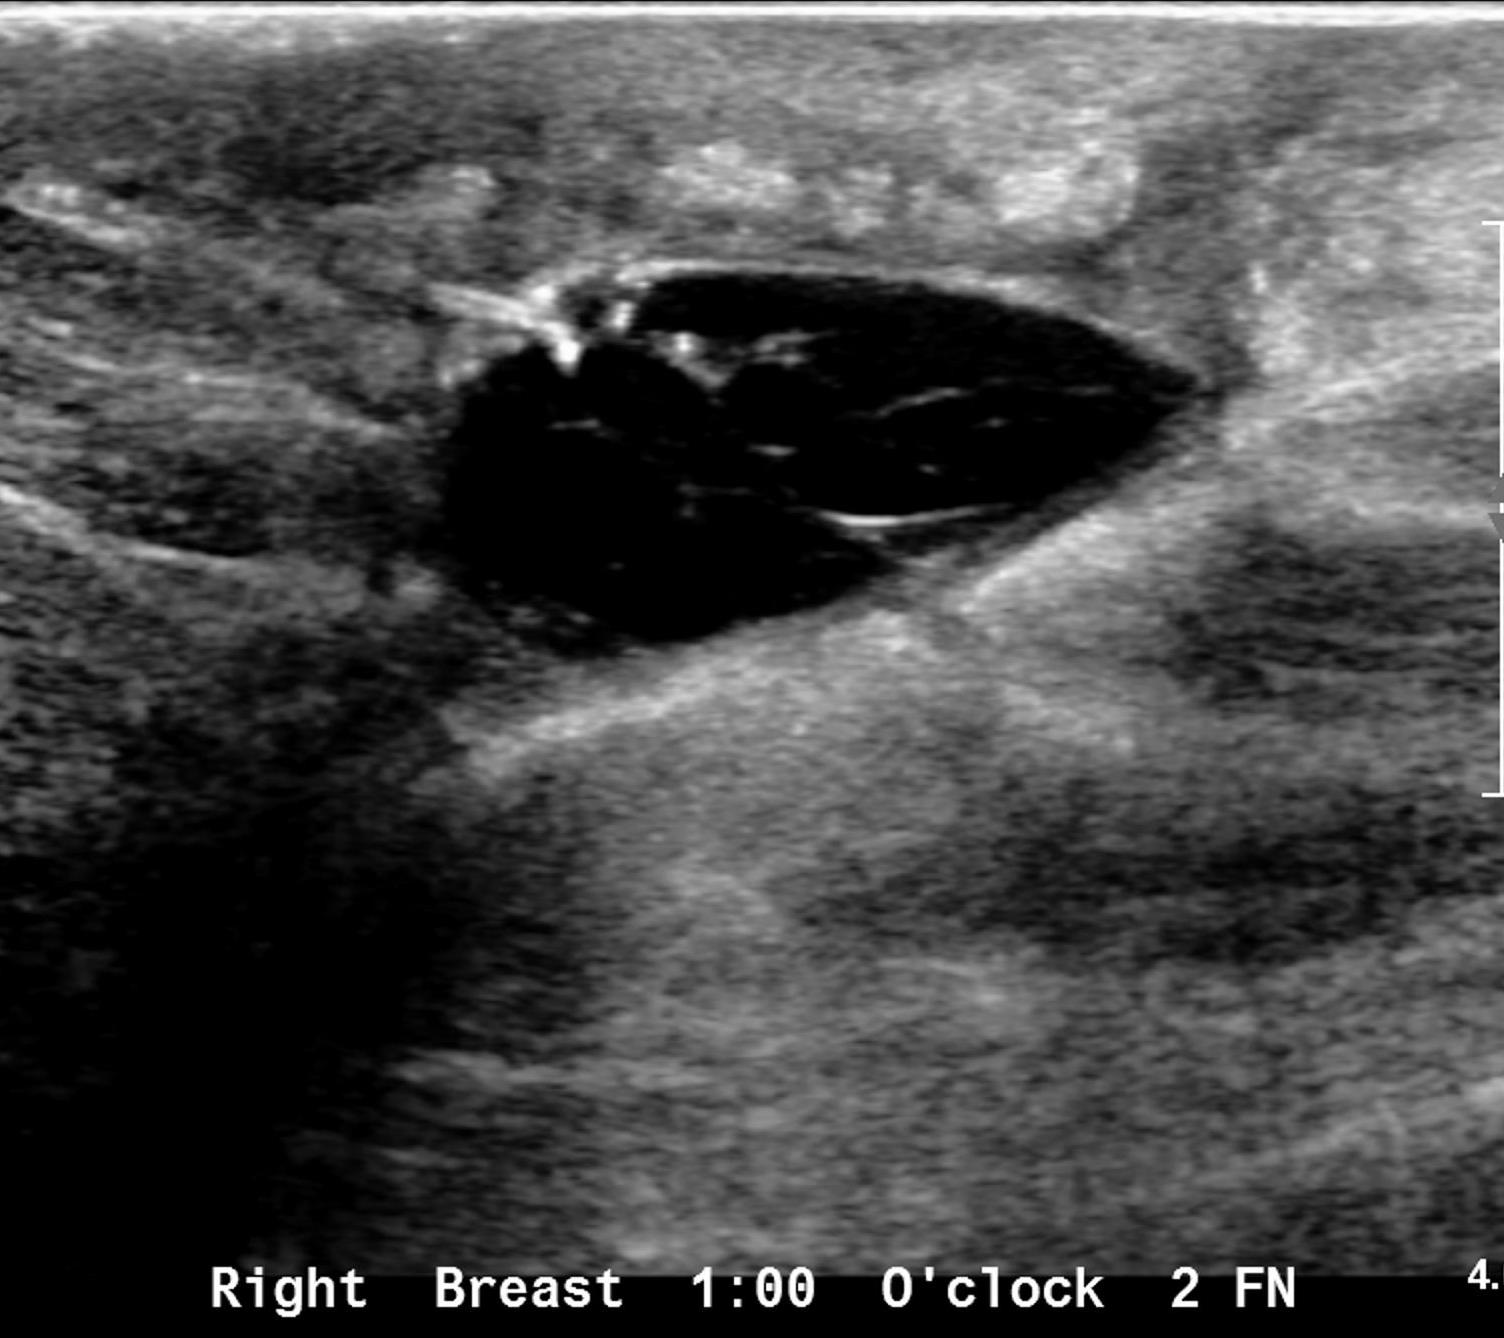

Ultrasound commonly shows irregular hypoechoic confluent mass with tubular extensions, circumscribed hypoechoic mass, skin thickening and edema with axillary lymphadenopathy having reactive features. Less common features include heterogeneous hypoechoic confluent masses with indistinct, lobulated or angular margins, parenchymal distortion with no discrete masses and heterogeneous parenchyma with edema. The lesions and surroundings show increased vascularity. The findings will be normal in 4-20% of the cases. With advanced disease, fluid collections or abscesses may be present.

Ultrasound showed at 12 o’clock position in retroareolar region, a complicated cyst with thick nodular wall measuring 4.4x3.1x5.0 cm. Right axilla showed two round LN with effaced hila measuring 0.6 cm.